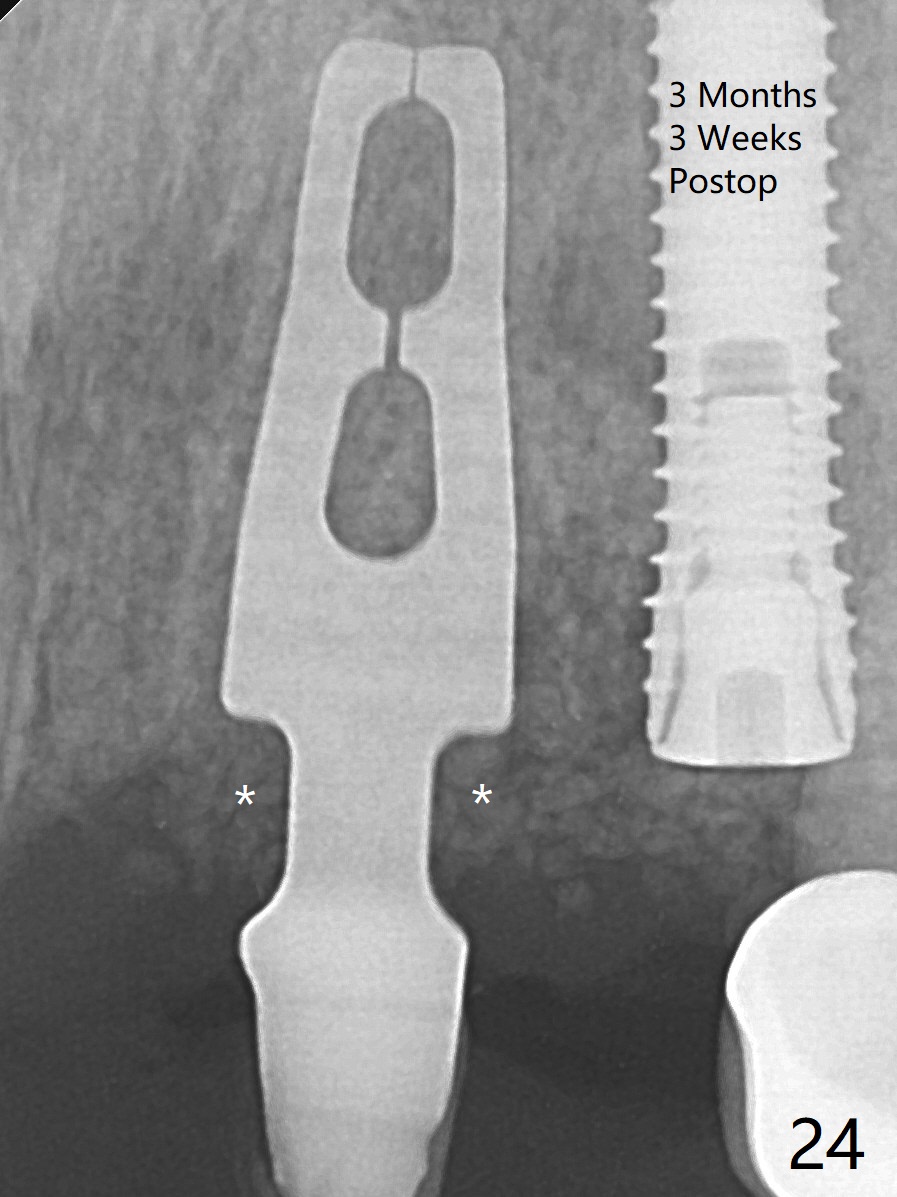

上前牙桥撤除显示右上1,2牙齿以及左上2叶片状植体好像可以保留,而左上3牙齿不能(图一,二(<:托牙边缘压迹)),拔除左上3牙齿后, 暂时把牙桥回位(图三:FPD(已经去除左上3号牙牙冠))作为3号牙种植位置参考(图四至六(G:骨粉))。其实植入前,当最后一个钻头还在原位,将PRF膜和粘性骨放置颊侧根尖(但愿骨粉能放深点),因为那里骨质很薄,好像缺损。由于植体扭力很低(大约5Ncm),放置骨粉覆盖植体(图七),为了不用缝线,涂牙周胶水(图八),放置胶原膜(图九),再涂胶水(图十)固定,最后利用右上1,2号牙(去龋,build-up后)和左上2植体制作临时牙桥,并且覆盖左上3牙槽窝。术后即刻CT显示植体颊侧(B)骨粉(图十一:*)。<:植体根尖仍有间隙,植体应该再长2毫米,初步稳定性会好些。左上3植牙愈合后,将与左上2植体制作左上1-3悬臂桥,右上1,2号牙将做根管治疗,桩,牙冠。临时牙桥术后十一天松动,右上一,二牙牙髓活性测定正常,深洗后,再次build up,不小心把左上3胶原膜吹掉,下面骨粉还稳定。术后三周病人回来做右上六种植,前牙临时修复体(图十二)需要修改(图十三)。拍摄三个方向照片显示前牙牙龈乳头(颊侧和咬合面)。

The mesiobuccal margin at #8 is redefined 4 weeks postop (Fig.14) so that the cervical end of the temporary crown is able to move mesially (Fig.13). The most coronal portion of the bone graft at #11 begins to be detached (*). The mesial portion of the abutment at #10 will be removed (curved white line) in the following week. After removing the most coronal portion of detaching bone graft at #11, acrylic is added to form a concave pontic (Fig.15 ^). With removal of the mesial portion of the abutment at #10, the retainer is moved distal (>). Pontics form at UL1 and 3 two months postop (Fig.16 *), while there is buccal atrophy at UL1,2 (Fig.17). 术后3个月植牙区牙龈形态良好(图十八),即将暴露,放置愈合基台。图十九是在右上1根管治疗时(基台放置后五天)拍摄。左上3术后3个月3个星期,1,2唇侧塌陷(图二十)。叶状植体处牙槽嵴往根尖萎缩(图二十一:^)。尽管做了松弛切口,放入事先预备的粘性骨粉后,几乎没有空间放置结缔组织移植物,恰好还没有取。放置PRF膜后,使用4-0 Monoglyc缝线缝合。牙龈似乎冠方移位(图二十二:箭头)。植骨后,唇侧仿佛饱满多了(图二十三:*)。骨粉放置于左上1,2唇侧和牙槽嵴(图二十四:*,与之前(图十九)对比)。后者有助于牙龈冠方移位,而前者有助于增加唇侧饱满度。植骨术后两周唇侧仍饱满(图二十五,六)。植骨后四个月牙冠粘固,两个月后,病人抱怨10号牙左右食物坎塞(图二十七),9/10牙冠撤除,10基台边缘加深,重做临时牙冠,同时增加9凹陷(pontic)。一个月后,9/10临时牙冠修整两次,11永久性牙冠撤除,也制备临时牙冠,外形明显改善(图二十八)。